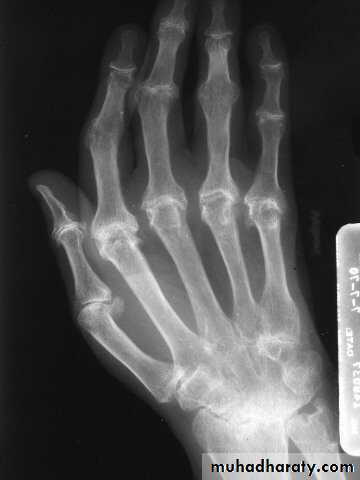

Severe erosive changes at radio-ulnar joints carpal bones at the metacarpal heads

Bilaterally symmetricSevere ulnar deviation

Severe erosions of MCPsComplete destruction of the wrist

Resorption of the carpals and the heads of the metacarpals

Radial deviation of the wrist

Rheumatoid wrist: articular destruction, carpal fusion and carpal collapse.